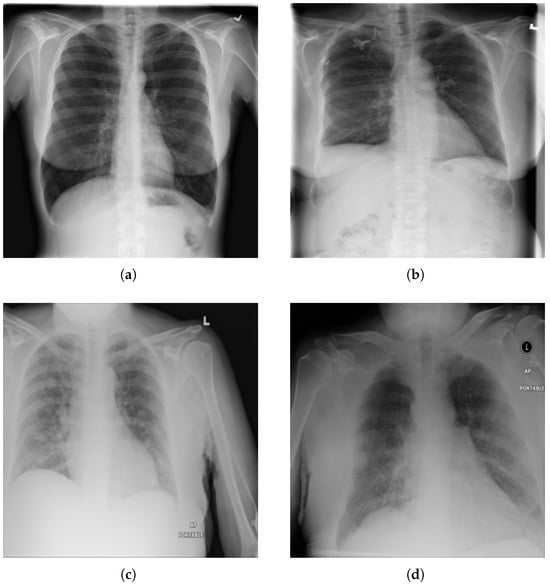

We have used the NIH Chest X-ray14 benchmark dataset [4], which is a well-known and widely used benchmark dataset. It contains a total of 112,120 frontal CXR images from 30,805 patients in Digital Imaging and Communications in Medicine (DICOM) format. For research purposes, the dataset is also made available in PNG format where each image has a resolution of 1024 × 1024 pixels. Out of the total, 86,524 images are allocated for training, and the remaining 25,596 are used for evaluation. There is no overlap in patients between the training and test datasets. The dataset includes 51,759 CXR images with 14 different disease labels in a multi-label format, meaning a single CXR image can exhibit more than one disease. Additionally, there are 60,361 CXR images of normal patients. The label frequencies are shown in Figure 3, which also indicates the class imbalance problem associated with the dataset and making it a challenging task. Moreover, some examples from the dataset along with the findings are shown Figure 4. For training purposes, all images were downscaled from their original resolution to 256 × 256 pixels using bicubic interpolation. Moreover, we split the training set randomly to create a validation set of 8652 images using a 90:10 ratio. Labels are coded using a multi-hot encoding scheme. For evaluation, we employ the standard performance metric proposed by Wang et al. [4], which is widely adopted by researchers for the NIH Chest X-ray14 dataset. Specifically, the area under the receiver operating characteristic curve (AUC) is computed for each class in the MLC.

Figure 4.

Examples from NIH chest X-ray14 datasets with labels: (a) No Finding, (b) Fibrosis. (c) Mass, and (d) Edema, Pleural Thickening, and Pneumonia.